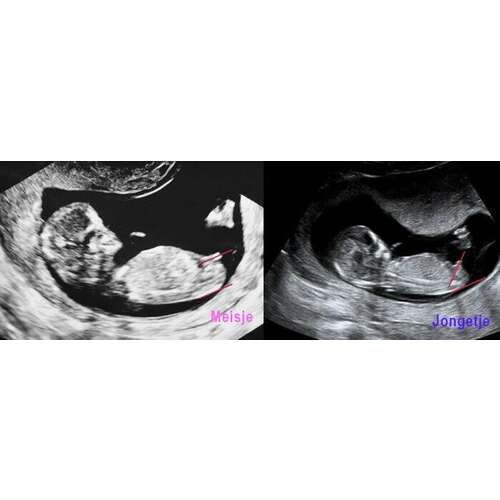

11+6 zou denken een meisje. Als het echt de NUB is haha.

Ik zou zeggen een meisje. Het gaat eerder richting -30掳 dan +30掳 馃槀

Ja dat is zo, neigt meer naar meisje dan.. nou... ben benieuwd!